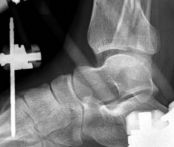

Temporary ankle-spanning external fixation was used to stabilize the fracture and soft tissues. X-rays taken after external fixation showed improved alignment and allowed for better understanding of the fracture pattern (Fig 2.2-2). Computed tomographic (CT) scanning with 3D reconstruction was performed for precise assessment of the fracture pattern of the tibial plafond. The CT revealed displaced fragments with a resultant intraarticular step-off and gap. The distal tibial metaphyseal fracture was multifragmentary. In addition, an associated long oblique fibular fracture was present (Fig 2.2-3).

Fig 2.2-3a–h A CT scan with 3D reconstruction.

a–d Sagittal (a–b), coronal (c), and axial (d) images demonstrate displaced posterior, anterolateral, and medial fracture fragments resulting in intraarticular step and gap. The incongruent tibiotalar joint is best appreciated on the sagittal scan.

e–h The 3D reconstructed images show the external fracture anatomy and general alignment.